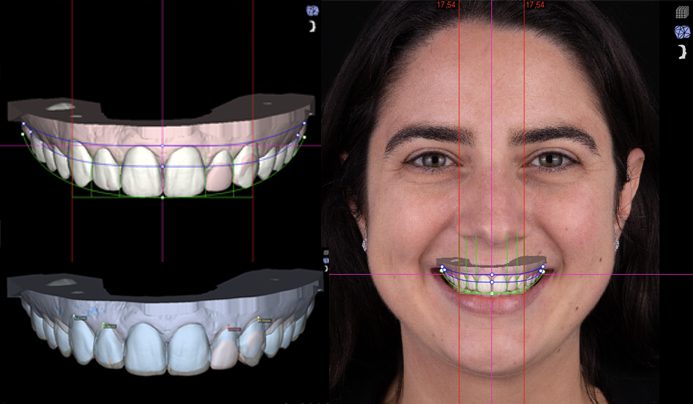

2️⃣ التحليل الرقمي

يتم تحليل:

- خط الابتسامة

- تموضع الأسنان

- تناسق الشفاه

- علاقة الأسنان بالوجه

3️⃣ التصميم الافتراضي

باستخدام برامج DSD المتقدمة، يتم:

- رسم الابتسامة المثالية

- تحديد الطول والعرض واللون

- محاكاة النتيجة النهائية بدقة عالية

4️⃣ العرض على المريض

يرى المريض ابتسامته الجديدة قبل بدء العلاج، مع إمكانية التعديل حسب الرغبة.